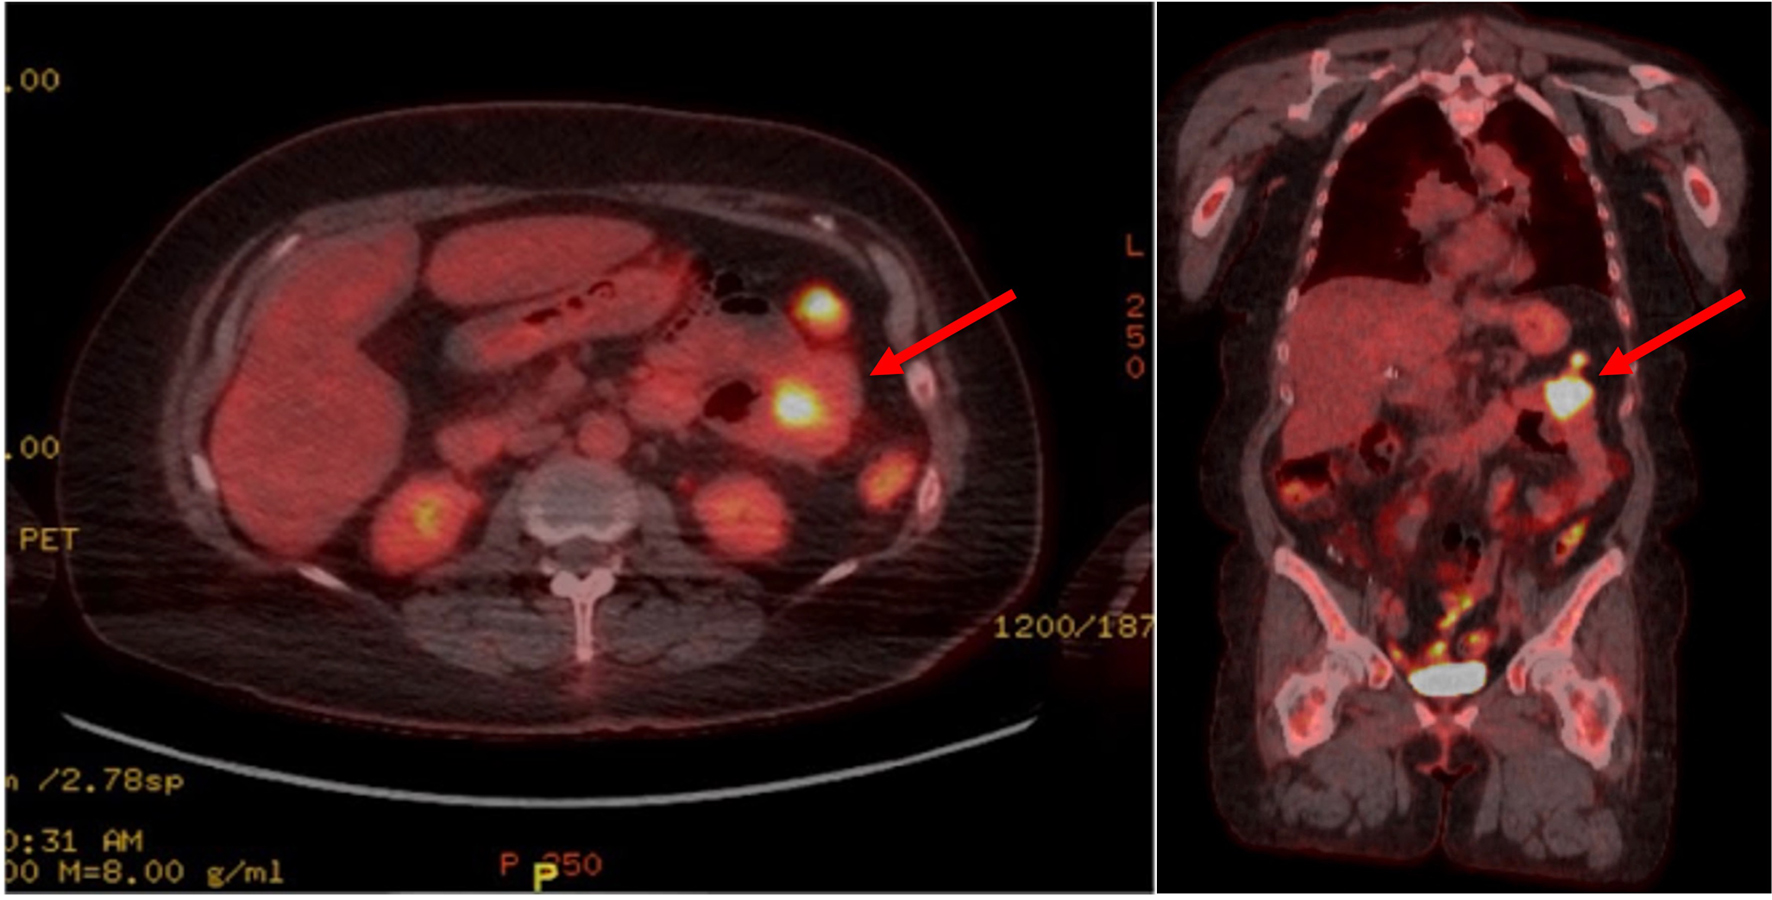

Several months after radiation to the adrenal gland, she developed a new hypermetabolic mass within the proximal small bowel and a new hypermetabolic nodule in the right upper lobe on a surveillance PET scan (Fig. 1). She was scheduled to have a percutaneous biopsy of the lung lesion; however, it was postponed due to acute onset of shortness of breath. She was found to have anemia with a hemoglobin (Hgb) of 5.5 and a hematocrit (Hct) of 18.3%. She previously noted occasional dark stools, although an initial esophagogastroduodenoscopy (EGDS) failed to demonstrate any acute bleeding or masses. She received several units of packed red blood cells (pRBCs) at that time. In the following weeks, she continued to struggle with persistent and severe anemia (Hgb 6.7, Hct 21.3%), for which she received another two units of pRBCs and was then admitted to the hospital for further evaluation.

![]() Click for large image | Figure 1. Axial (left) and coronal (right) views of a PET scan showing a hypermetabolic mass in the left upper quadrant small bowel loop (depicted by the red arrows), demonstrating a maximum SUV of 16.5 and measuring 2.9 cm in width. PET: positron emission tomography; SUV: standardized uptake value. |